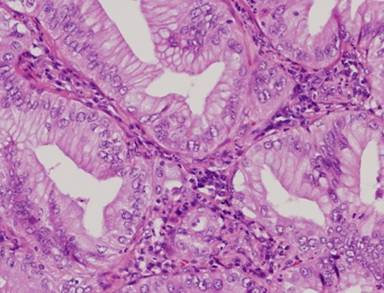

Histopathological examination of the resected lung mass showed that the tumor was composed of large, clear columnar epithelial cells arranged in atypical glandular structures. These morphological features were similar to those of the previously resected pancreatic cancer, and lung metastasis of pancreatic cancer was strongly suspected (Figures 4 and 5).

|

Figure 5. Metastatic lung cancer specimen (x200). The tumor was composed of large, clear columnar epithelial cells arranged in atypical glandular structures. These morphological features are similar to those of previously resected pancreatic cancer. So, we diagnosed that pulmonary tumor was metastatic. |

Immunohistochemically, the tumor was positive for cytokeratin (CK) 7, and negative for CK20 and thyroid transcription factor-1 (TTF-1), consistent with a diagnosis of lung metastasis of pancreatic cancer.